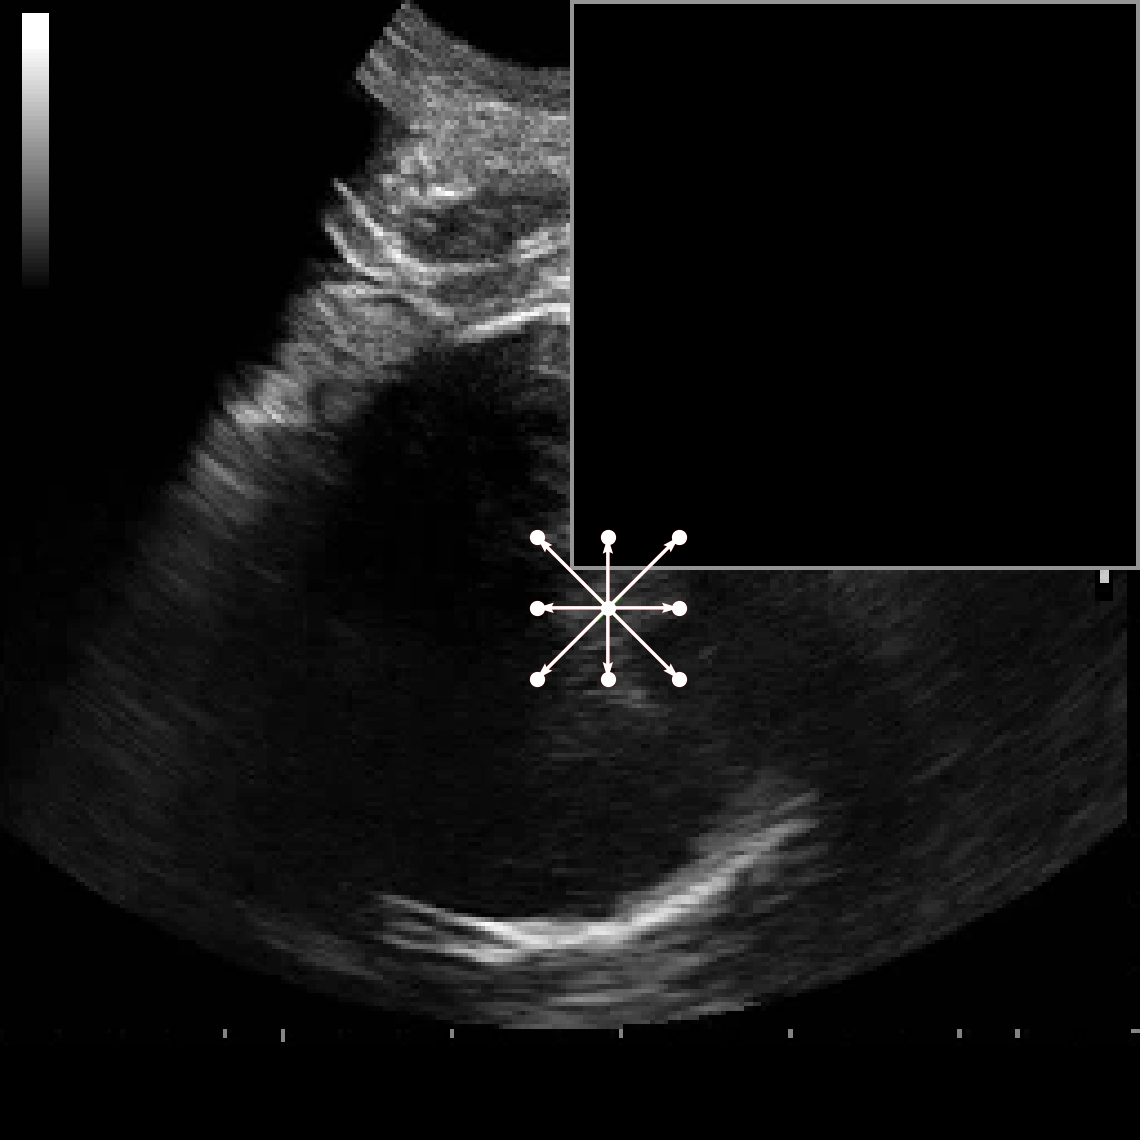

Figure 4 and Figure 5 provide visual comparisons of segmentation masks generated by DAUNet and other competing methods on representative samples from both datasets. As illustrated in Figure 4, DAUNet produces more accurate and smoother boundary delineations, closely aligning with the ground truth annotations, even in challenging low-contrast regions or under partial occlusion. A similar performance can be observed in Figure 5, where proposed model accurately identify the pulmonary embolism regions. It is worth nothing that the proposed model achieve best performance in two different imaging modalities, consisting of different sized regions of interest and number of classes demonstrating a good generalization.